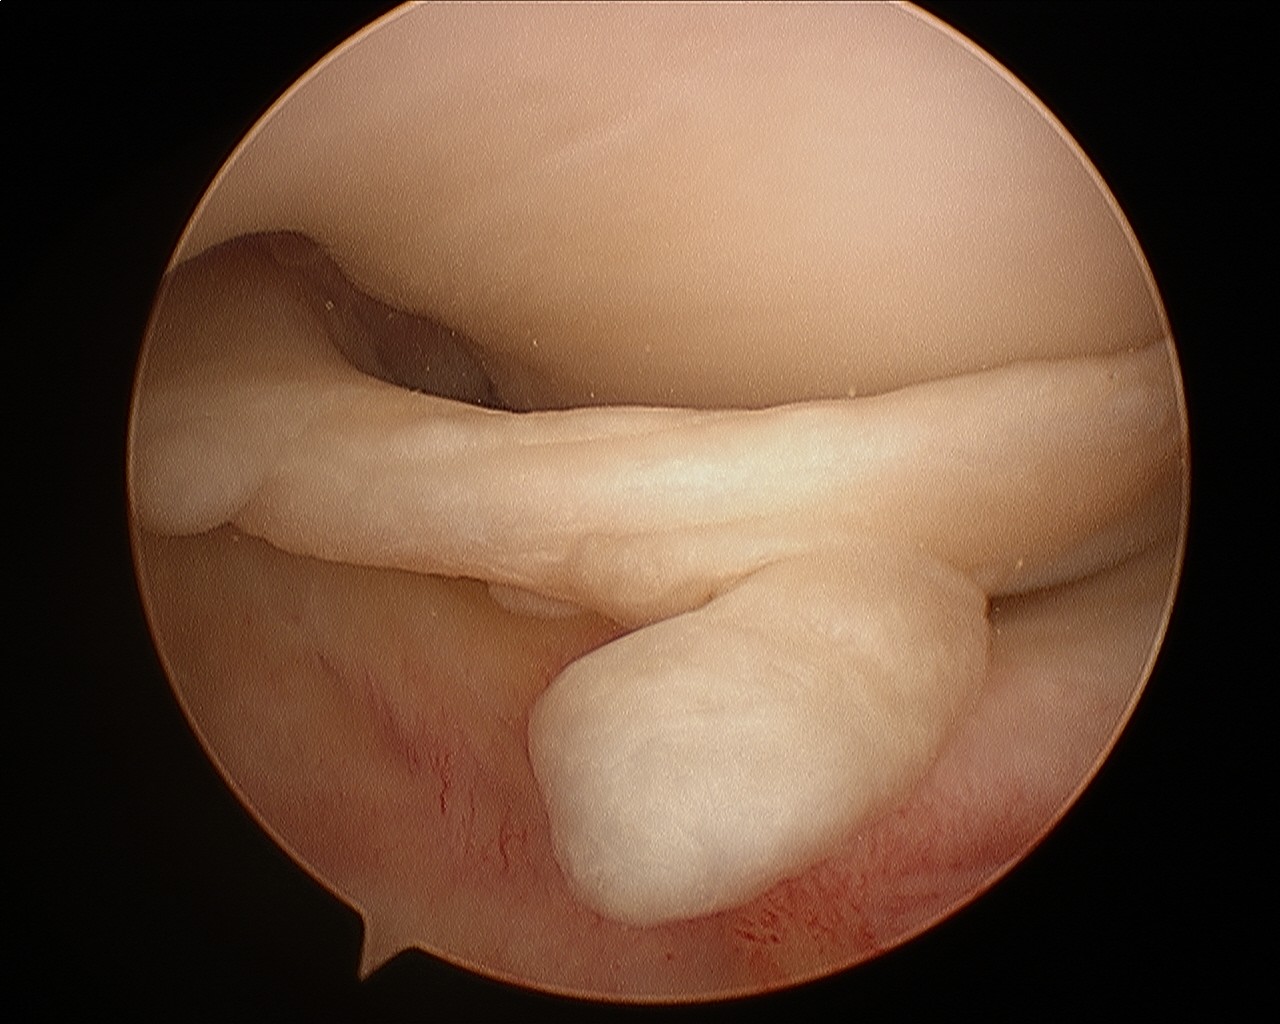

Knee Arthroscopic pictures showing

Normal ACL

Normal Meniscus and Normal Knee Surface Cartilage

Meniscal tear

Loose Body

Absent ACL (empty notch)